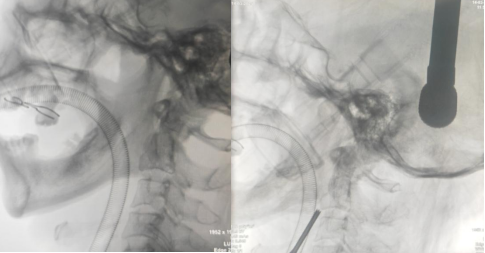

患者韦某某,男性,60岁,因高处坠落至颈部疼痛,来到我院脊柱外科就诊。经详细影像学检查,诊断为II型枢椎齿状突骨折。在与家属充分沟通并经过周密的术前准备,通过脊柱外科副主任、博士研究生、主任医师张鹭的指导和麻醉与围术期医学科和脊柱外科医护人员的通力配合下,手术顺利进行。术中首先在透视下进行牵引复位,再通过术中可移动3D C臂对患者骨折部位进行扫描,然后在电脑中模拟规划螺钉植入的位置,利用手术机器人机械臂进行导航精准植入1枚齿状突拉力螺钉,使患者的骨折得到良好的复位固定。张鹭表示:前路骨折固定的优点是能够调整患者保持C1~C2的活动度,大概占颈椎旋转功能的50%,另一优点为骨折融合率为80%~95%。目前,在骨科机器人的辅助下,可利用机械臂精准导入从颈椎前方进行螺钉固定,具有创伤相对小、恢复快的特点,使手术更加精准、稳定,保证了手术的安全性。

术中牵引复位

术中规划螺钉位置

术中使用机械臂辅助置入螺钉

术中复查CT见螺钉位置满意达到规划位置